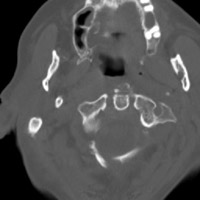

- Click on the image for a larger versionCAxial CT. The image shows the fracture of the posterior arch of C1.